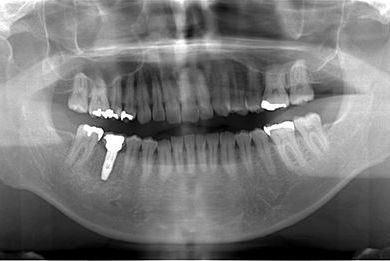

インプラントの症例写真 IMPLANT

抜歯即日スピードインプラント治療

| 性別/年齢 | 男性 / 38歳 | ||||||||||||||||||||||||||||||||

| 主訴 | 10年位前に虫歯治療をした右下奥歯のつめ物が取れ、再治療を受けた際にインプラントをすすめられたため、治療相談で来院。 | ||||||||||||||||||||||||||||||||

| 治療方針 | 抜歯と同時にインプラントを埋入し、治療期間を短縮する。 | ||||||||||||||||||||||||||||||||

| 治療内容 | インプラント1本(抜歯即日スピードインプラント)、ハイブリッドセラミッククラウン1本 | ||||||||||||||||||||||||||||||||